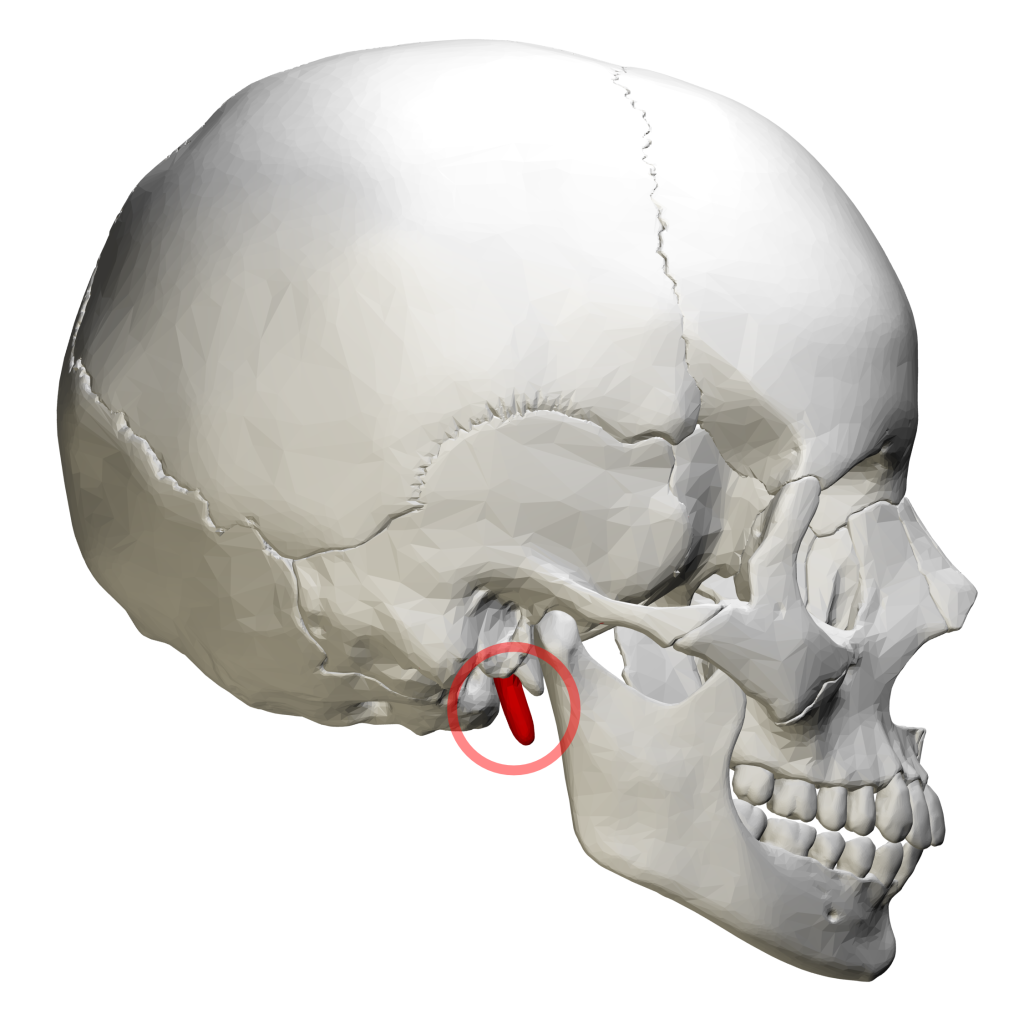

إن متلازمة النسر ، والتي تعرف أيضاً بمتلازمة ايجل أو متلازمة تطاول النتوء الإبري، هي متلازمة نادرة تسبب ألماً في منطقة الوجه أو الرقبة، حيث يكون هذا الألم ناتج عن وجود مشاكل في عظمة النتوء الإبري أو الرباط الإبري اللامي. والجدير بالذكر أن عظمة النتوء الإبري هي عظمة صغيرة مدببة تقع تحت الأذن مباشرة، والتي ترتبط من خلال الرباط الإبري اللامي مع العظم اللامي المتواجد في الرقبة.

إن متلازمة النسر قد تحدث لدى معظم الناس بسبب وجود زيادة غير طبيعية في مقدار طول عظمة النتوء الإبري، حيث قد يحدث ذلك نتيجة لـ:

أيضاً قد تحدث هذه المتلازمة بسبب وجود تكلس في الرباط الإبري اللامي. والجدير بالذكر أنه بالرغم من أن متلازمة النسر يمكن أن تؤثر على الأشخاص من كلا الجنسين وجميع الأعمار، إلا أنها أكثر شيوعًا في النساء بين سن 40 – 60.